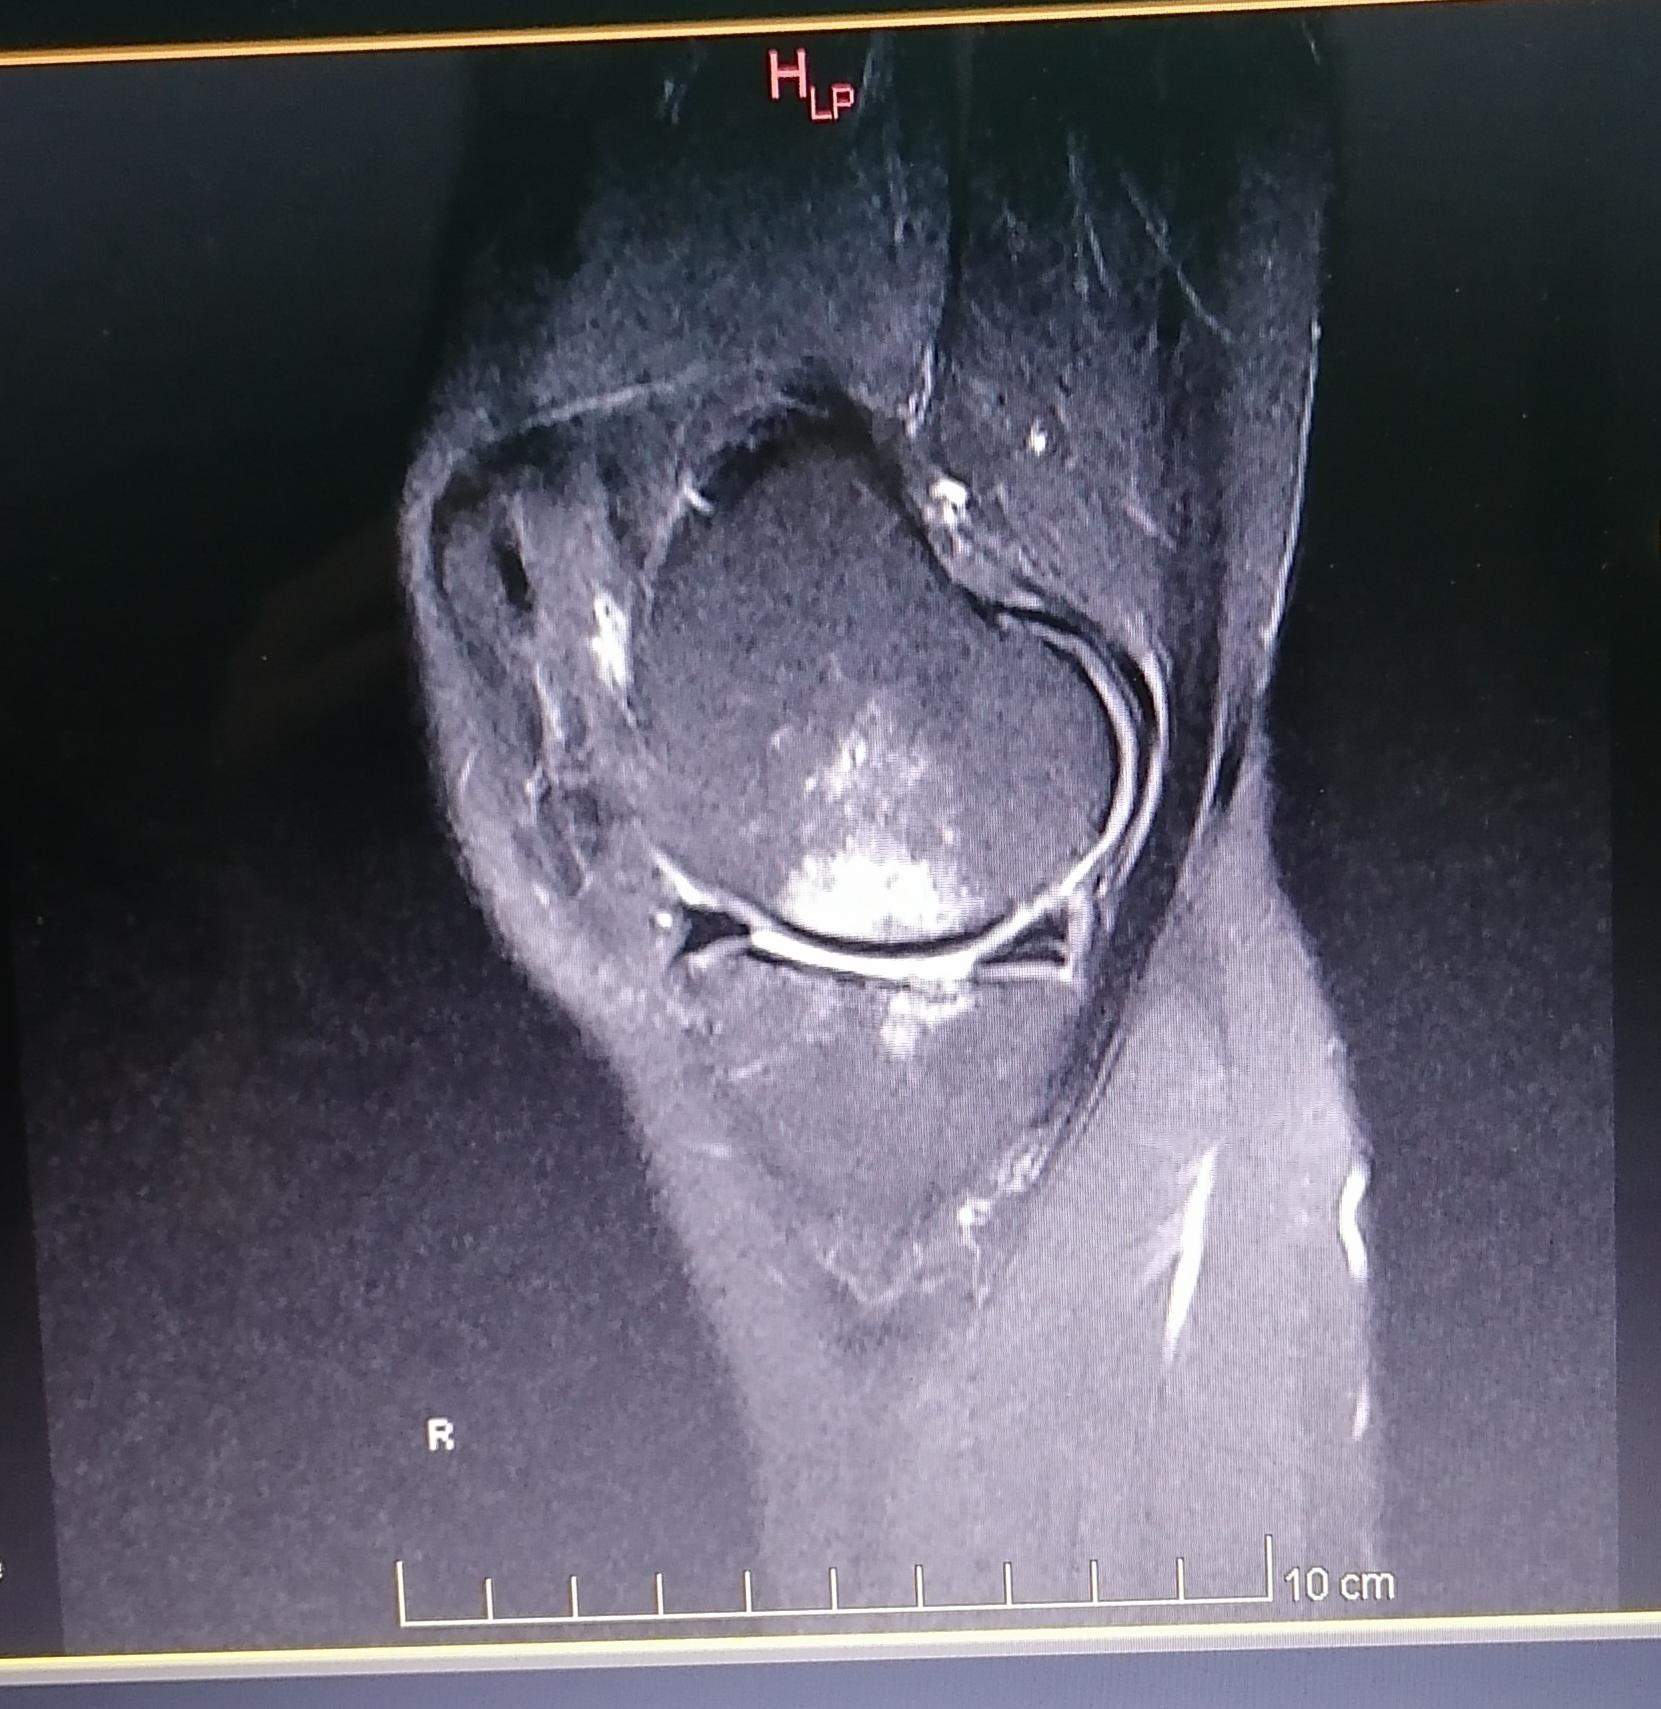

Kann mir jemand bei der Auswertung von MRT Bildern am Knie geben? (Arzt, Bluterguss, Radiologie)

MRT Befund rechtes Knie ist da irgendwie ne OP notwendig?

Meniskus gerissen MRT? (Knie, MRT Befund, Radiologie)

MRT Knie, weiße Schatten + Meniskusriss? (Schmerzen, Befund, Kniegelenk)